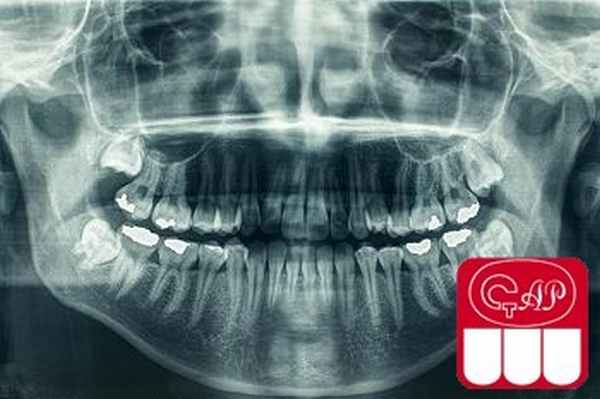

Холодовая проба отрицательная. Визуально заметная стертость окклюзионных поверхностей наблюдается только в области нижних резцов младшей сестры. Кариесом поражен только один зуб у старшей сестры. При рентгенологическом исследовании сразу же обращает на себя внимание полная облитерация полостей зубов (рис. 4).

Рис. 4. ОПТГ младшей сестры.

Только у младшей сестры в области экватора коронок нижних третьих моляров определяется просветление в виде узких горизонтальных полосок. Второе, что привлекло наше внимание на ОПГ, — низкая рентгеноконтрастность дентина, из-за чего контуры корней ряда зубов «размыты». Третья особенность — необычно малая и, наоборот, необычно большая длина корней у некоторых зубов. Четвертая особенность — из-за контраста между широкими коронками и узкими шейками зубы имеют сходство с луковицами, особенно премоляры и моляры старшей сестры. Определяется горизонтальная линия перелома в области верхушечной трети корня зуба 1.1 у старшей сестры, а также штифтовые конструкции, оси которых не совпадают с осями корней, в зубах 1.1 и 2.1 у младшей сестры. И последнее — имеются нечетко определяемые участки просветления округлой формы у верхушек корней некоторых зубов.